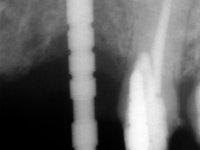

66-year-old male patient, non-smoker. It featured a 5-member metal-ceramic bridge with extreme mobility. Teeth 11 and 21 had infiltrated cervical margins. Both arches showed root exposure with signs of cervical abrasion. Composite resin “slots” were visible on the buccal surfaces of some mandibular teeth compatible with an orthodontic treatment with aligners that the patient was undergoing. After the imaging examination, it was found that the bridge's distal support, tooth 24, was irretrievably lost. The mesial pillars 11 and 21 had endodontic treatment and intraradicular posts. Teeth 25 and 26 also had endodontic treatment and extensive restorations in composite resin. In the lower jaw, two bridges were visible. In the third quadrant a 4-element bridge supported on tooth 35 and on 2 implants placed in the location of teeth 36 and 37. In the fourth quadrant a 3-element bridge supported on tooth 45 and an implant placed in the location of tooth 46. The patient presented a thick gingival phenotype and very good oral hygiene.

A temporary acrylic bridge made in the laboratory with 7 elements was made, with teeth 11,21, 25 and 26 as pillars. The old bridge was removed and tooth 24 was extracted. The provisional bridge after relining was cemented in the mouth. Two implants were placed in the teeth 22 and 24 and 3 months after this intervention an impression was made to make a temporary bridge screwed over the implants and cemented to the teeth. The bridge was placed in the mouth and teeth 25 and 26 were extracted. 3 months later, surgery was performed to fill the maxillary sinus and 6 months later the implant was placed in the location of tooth 26. After osseointegration of this implant, the final impression was made for the final work. The bridge over the implants was permanently screwed on and the bridge over the teeth was cemented with resin-reinforced glass ionomer cement.